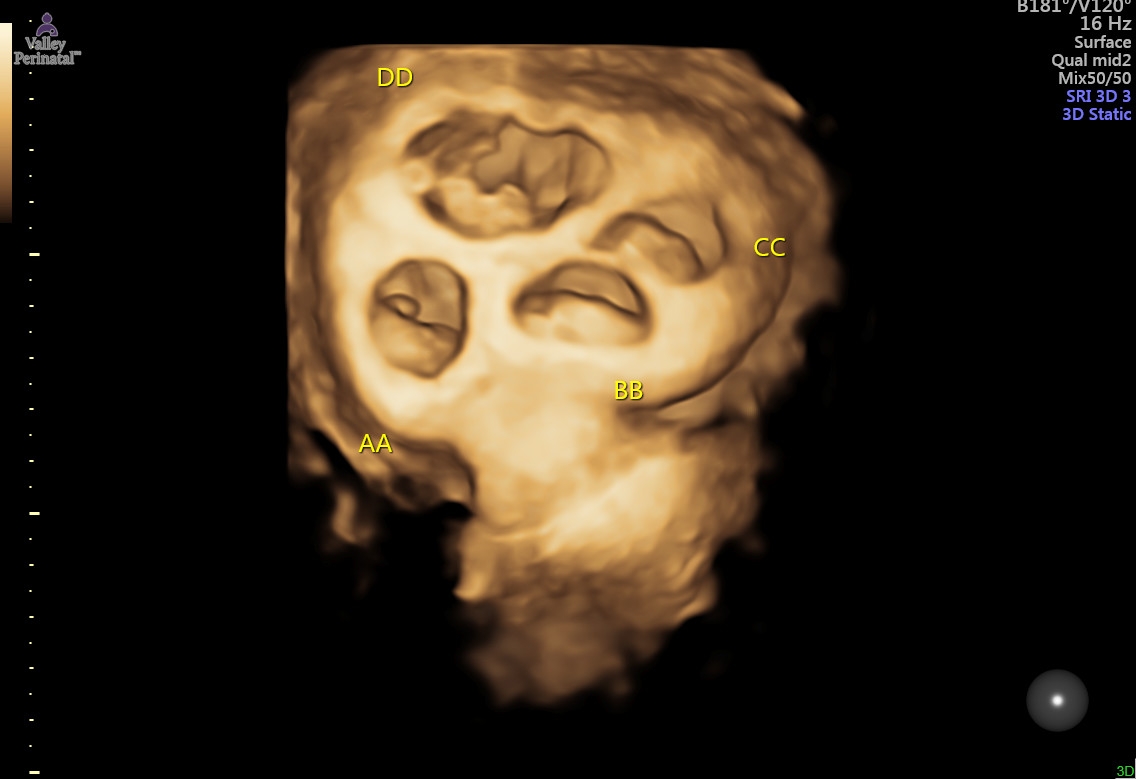

We had our first perinatalogist appointment last week and they were amazing at how well the babies were measuring and heartbeats were good and strong. All babies are measuring the same size and none are measuring small which is very rare according to the drs. They discussed that I will most likely be put on bedrest by 20 weeks which makes me feel like my time is quickly dwindling to get things done and squeeze some last only child tims in with my son.

I have attached the latest ultrasound image to make up for my absence!